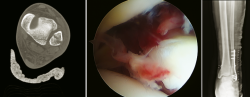

Figura 4. Lesión osteocondral en paciente con inestabilidad crónica de tobillo. Reparación directa, perforaciones y malla de condrocitos por vía artroscópica.

- Cirugía artroscópica: lesiones osteocondrales, tratamiento artroscópico de la inestabilidad (reparación y técnicas de reconstrucción), endoscopia posterior de tobillo y tendoscopia (Figuras 4, 5, 6 y 7).